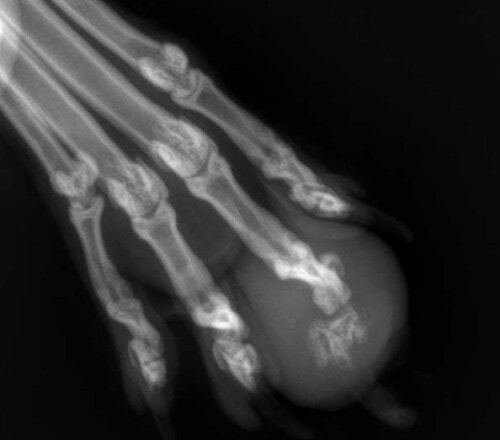

– la radiographie de l’extrémité podale met en évidence un gonflement des tissus mous et une ostéolyse de la dernière phalange, évoquant préférentiellement un envahissement tumoral (primitif ou métastatique)

Photo 3: Ostéolyse de la dernière phalange du doigt III